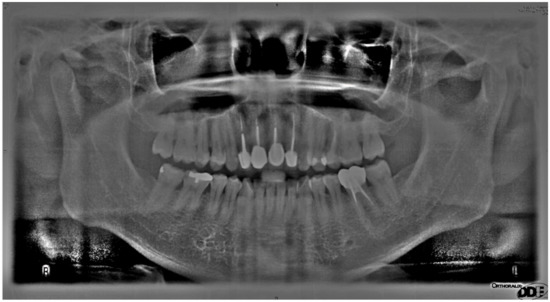

| Image Enhancement in Cutting Accuracy Rate | |||||

|---|---|---|---|---|---|

| Original Image | Matrix Operation Diagram | Image Contrast Adjustment | Flat-Field Correction | Adaptive Histogram Equalization | |

| Cutting accuracy rate | 34.72% | 51.68% | 58.74% | 78.61% | 89.95% |